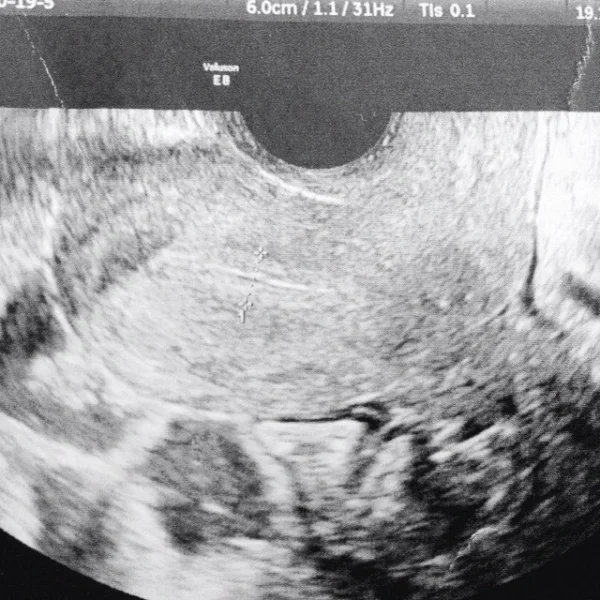

Congélation et décongélation des embryons

La congélation des embryons offre de nombreux avantages aux couples qui demandent un traitement de fécondation in vitro. Après le transfert d’embryons, les embryons restants sont suivis par des embryologistes et s’ils sont aptes à la congélation, ils sont congelés et conservés dans de l’azote liquide à -196°C, avec l’accord écrit du couple. Lorsque les embryons congelés doivent être décongelés, ils sont retirés de l’azote liquide, décongelés à température ambiante, séparés du liquide protecteur, placés dans un environnement de culture spécial et placés dans un incubateur (appareils dans lesquels les embryons sont conservés). Le même jour, les embryons qui semblent en bonne santé sont transférés à la future maman.

Tout d’abord, l’endomètre doit être préparé a recevoir l’embryon,. Nous effectuons ce processus de préparation chez certaines patientes sous des médicaments contenant des œstrogènes et attendons que l’endomètre s’épaississe en formant 3 couches. Le transfert est généralement prévu 3 à 5 jours après l’ovulation ( Cela dépend de l’âge de l’embryon ). La muqueuse utérine est surveillé durant tout le long du processus. Une fois les embryons transférés, nous commençons un traitement de soutien à base de progestérone.